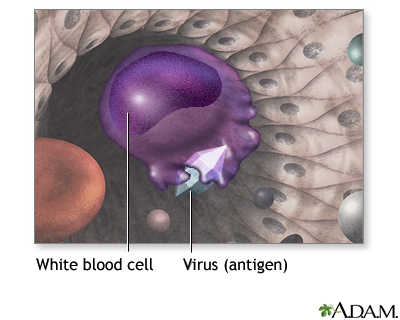

Your body is designed to protect you from infections. When you are exposed to a virus, bacterium, or other microbe, your immune system actually "learns" from the experience. The next time your body is exposed to the same microbe, your immune system often recognizes it and sets out to destroy it.

During immunization, you are exposed to an inactive/weakened microbe or a very small and safe amount of part of a microbe. Your body's immune system responds to the vaccine by making substances called antibodies. If you are exposed to the microbe itself at a later time, the antibodies will kill the microbe and prevent infection or you may have a milder infection.